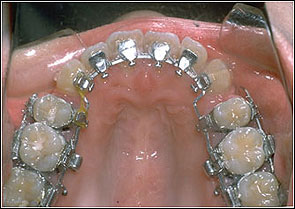

STEP 5. Detailing and finishing procedures

Stainless Steel with hook 016, 016*022, 017*025